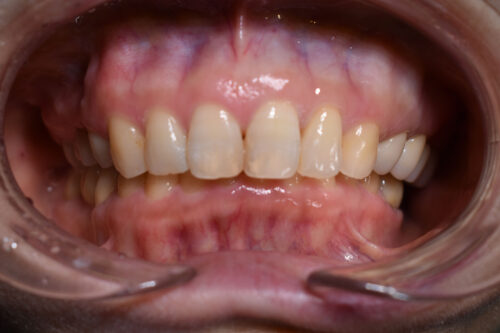

ワイヤー矯正治療1年2か月後です。

全額矯正治療 88万円、3~4週に一回来院

歯科矯正用アンカースクリュー(デュアル・トップオートスクリュー)上顎左右2本(25000円x2本分 提携医院にて)

ワイヤー期間 14か月, 17回来院